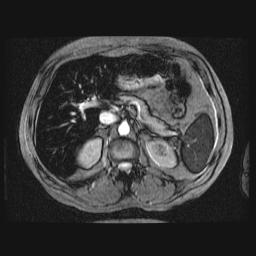

Foie Normal (Signa 1,5T)

Copyright - Yves Gandon - Imagerie Médicale -Rennes.